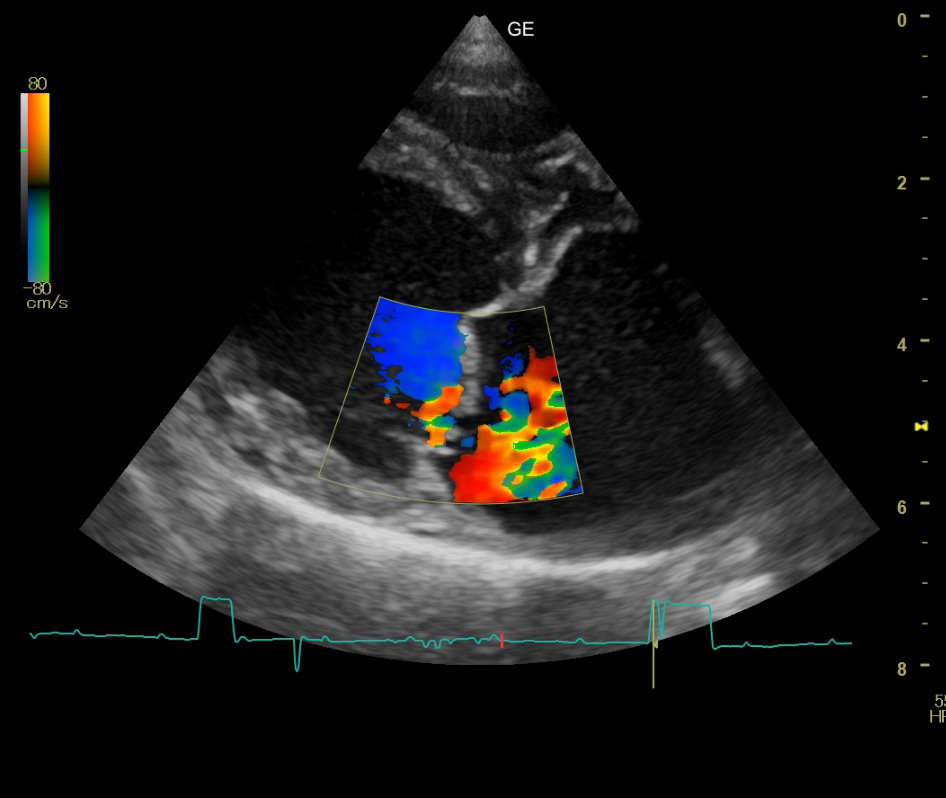

心エコー検査

心エコー検査では、超音波を用いて心臓の形態や動きをリアルタイムで観察できます。

心エコー検査は、

- 心臓の大きさ

- 心臓の壁の厚さ

- 弁の状態

- 血流の様子

などを詳細に評価できます。

非侵襲的で痛みを伴わず、短時間で行えるため、循環器疾患の診断に欠かせない検査です。